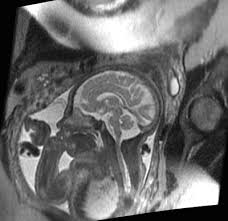

fetal mr nedir ve fiyatlari 2021 safir gorunteleme